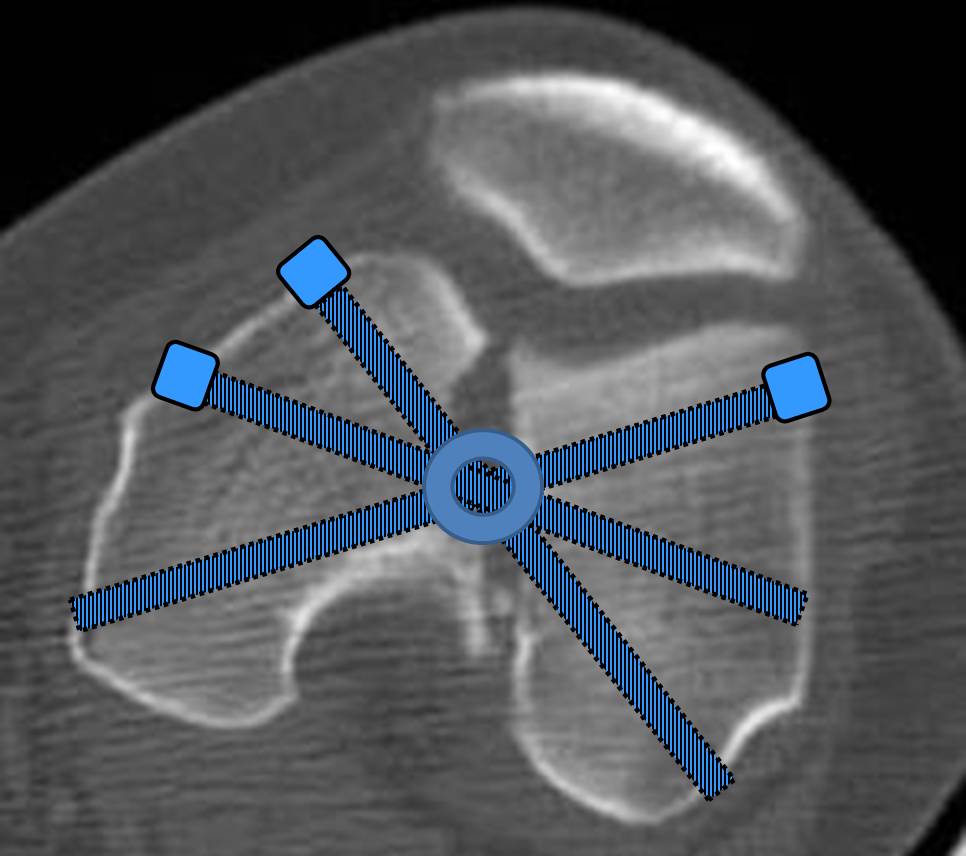

И уже лет шесть мы используем возможность ввести в дистальное овальное отверстие 3 винта, которые именно запираются в этом отверстии, не люфтят, а обеспечивают угловую стабильность - см картинку.

Получается и стабильно, и очень дистально, нижний край отверстия в 3 мм от дистального конца гвоздя.

С моей точки зрения, безусловная ценность предложенного Вами, Александр Николаевич, стержня состоит в возможности введения блокирующих винтов максимально близко к суставной поверхности дистального отломка, что значительно расширяет показания для применения интерлокинга. Можно предположить, что в техническом плане таким образом ввести блокирующие винты является непростой задачей. Кроме того, все они расположены в одной плоскости на небольшом расстоянии друг от друга.

Мне представляется, что конструкция с максимальными прочностными характеристиками будет иметь вид предложенной во вложенном файле. Такую конфигурацию расположения блокирующих отверстий на дистальном конце имеет стержень для большеберцовой кости фирмы ChM. Для бедренной кости такой стержень мне неизвестен. Поэтому в необходимых случаях (хорошо, что такие случаи встречаются не часто), как вариант, мы используем custom made стержень.

Наш гвоздик, выпускаемый предприятием ЦИТО, тоже скорее из универсальных, хотя и с расширенными возможностями для дистальных переломов. Это овальное отверстие внизу задумывалось как динамическое для высоких переломов, очень дистально его разместили, чтобы не опасаться перелома гвоздя по этому отверстию. А возможность вот такого введения винтов, образующих "сборный клинок", обнаружилась года через 3 его применения.

Но практика показывает, что классификации существуют не зря, и стоит пользоваться ими, а не ориентироваться на абстрактные "максимально низкие переломы". Подавляющее большинство поступающих к нам больных с дистальными переломами - это C1 и С2. И показанный в прошлом сообщении гвоздик прекрасно справляется. Наверно, сгодятся и многие современные гвозди разных производителей, типа RAFN Synthes. А вот при настоящих C3 одним гвоздем не обойтись, нужны как минимум винты мимо, а то и введение на одном уровне нескольких винтов и/или спиц веером...